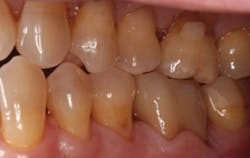

Figures 2 and 3: Additional restorations using Lava Esthetic